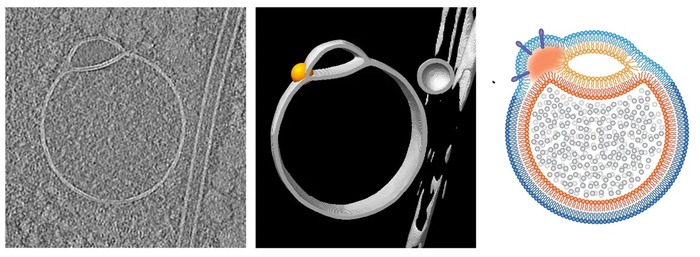

აქამდე უცნობი ორგანელები მაშინ შენიშნეს, როცა უჯრედთა ფორმის შემანარჩუნებელ ძაფოვან სტრუქტურებს, ფილამენტებს, იკვლევდნენ. ისინი სამგანზომილებიან გამოსახულებებში ხშირად ჩნდებოდა, თუმცა თავდაპირველად სურათის ხარვეზად მიაჩნდათ. მოგვიანებით გაირკვა, რომ ისინი რეალური იყო, თანაც, შესაძლებელია, ადამიანის უჯრედებში ცილების გადამუშავებასა და კონტროლში მნიშვნელოვან როლს ასრულებდეს.

ჰემიფუსომების ფორმა უჩვეულოა: ერთმანეთზე მიმაგრებული დიდი და პატარა სფეროსებრი სხეულები, რომელთაც ვიწრო მიჯნა ყოფს.

ამ ორგანელების დიამეტრი მხოლოდ დაახლოებით 100 ნანომეტრია, ანუ მიტოქონდრიაზე ნახევარჯერ და უფრო მეტჯერ პატარაა. ისინი მეცნიერებმა კრიოელექტრონული ტომოგრაფიის მეშვეობით დააფიქსირეს, რა დროსაც უჯრედებს ყინავენ, რათა მათი სტრუქტურა მაქსიმალურად შენარჩუნდეს. ეს მკაფიო სამგანზომილებიანი სურათების გადაღებას ხდის შესაძლებელს.

გამოცემა Nature Communications-ში გამოქვეყნებული ნაშრომის ავტორები ამბობენ, რომ აქამდე ჰემიფუსომების აღმოჩენა ტრადიციული მეთოდებით გამოსახულების გადამუშავების პროცესის გამო ვერ ხერხდებოდა. ასევე, ეს ორგანელები ზედმეტად პატარაა იმისთვის, რომ სხვა ტექნიკებითაც მკაფიოდ გამოჩენილიყო.

ისინი ერთგვარი ვესიკულებია — ბუშტის მსგავსი სტრუქტურები, რომელთაც უჯრედებს შორის ცილები და ჰორმონები გადააქვს. ჰემიფუსომები ამგვარი ვესიკულების ნახევრად შერწყმული წყვილის უჩვეულო კონფიგურაციას ქმნის (ამას ეფუძნება თავად სახელიც), მათ მიჯნაზე კი ცხიმოვანი ფენაა. სპეციალისტებს ეს აღმოჩენა მნიშვნელოვნად მიაჩნიათ, რადგან მსგავსი სხეულების არსებობის შესახებ ვარაუდები გამოთქმული იყო, თუმცა ცოცხალ უჯრედში მხოლოდ ახლაღა დაფიქსირდა.

მათი თქმით, ჰემიფუსომები ორგანელებად კლასიფიცირდება, ვინაიდან ისინი უჯრედის დამოუკიდებელი ფუნქციური ერთეულებია და არა დროებითი მემბრანული წარმონაქმნები. ეს ვესიკულები არც გაყინვის შედეგად ფორმირებული წანაზარდებია. უკანასკნელი კვლევით მათი ზუსტი როლი, სიცოცხლის ციკლები ან შედგენილობა არ დაუდგენიათ.